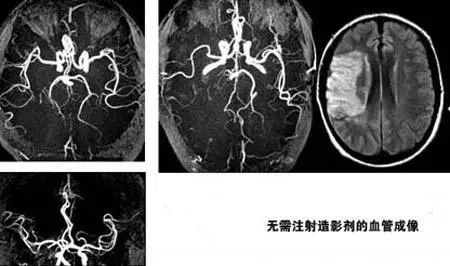

(5) 无需使用对比剂即可显示血管结构等优点。

(6) 磁共振对检测脑内血肿、脑外血肿、脑肿瘤、颅内动脉瘤、动静脉血管畸形、脑缺血、椎管内肿瘤、脊髓空洞症和脊髓积水等颅脑常见疾病具有非常高的诊断价值,同时对腰椎椎间盘后突、原发性肝癌等疾病的诊断也很有效。